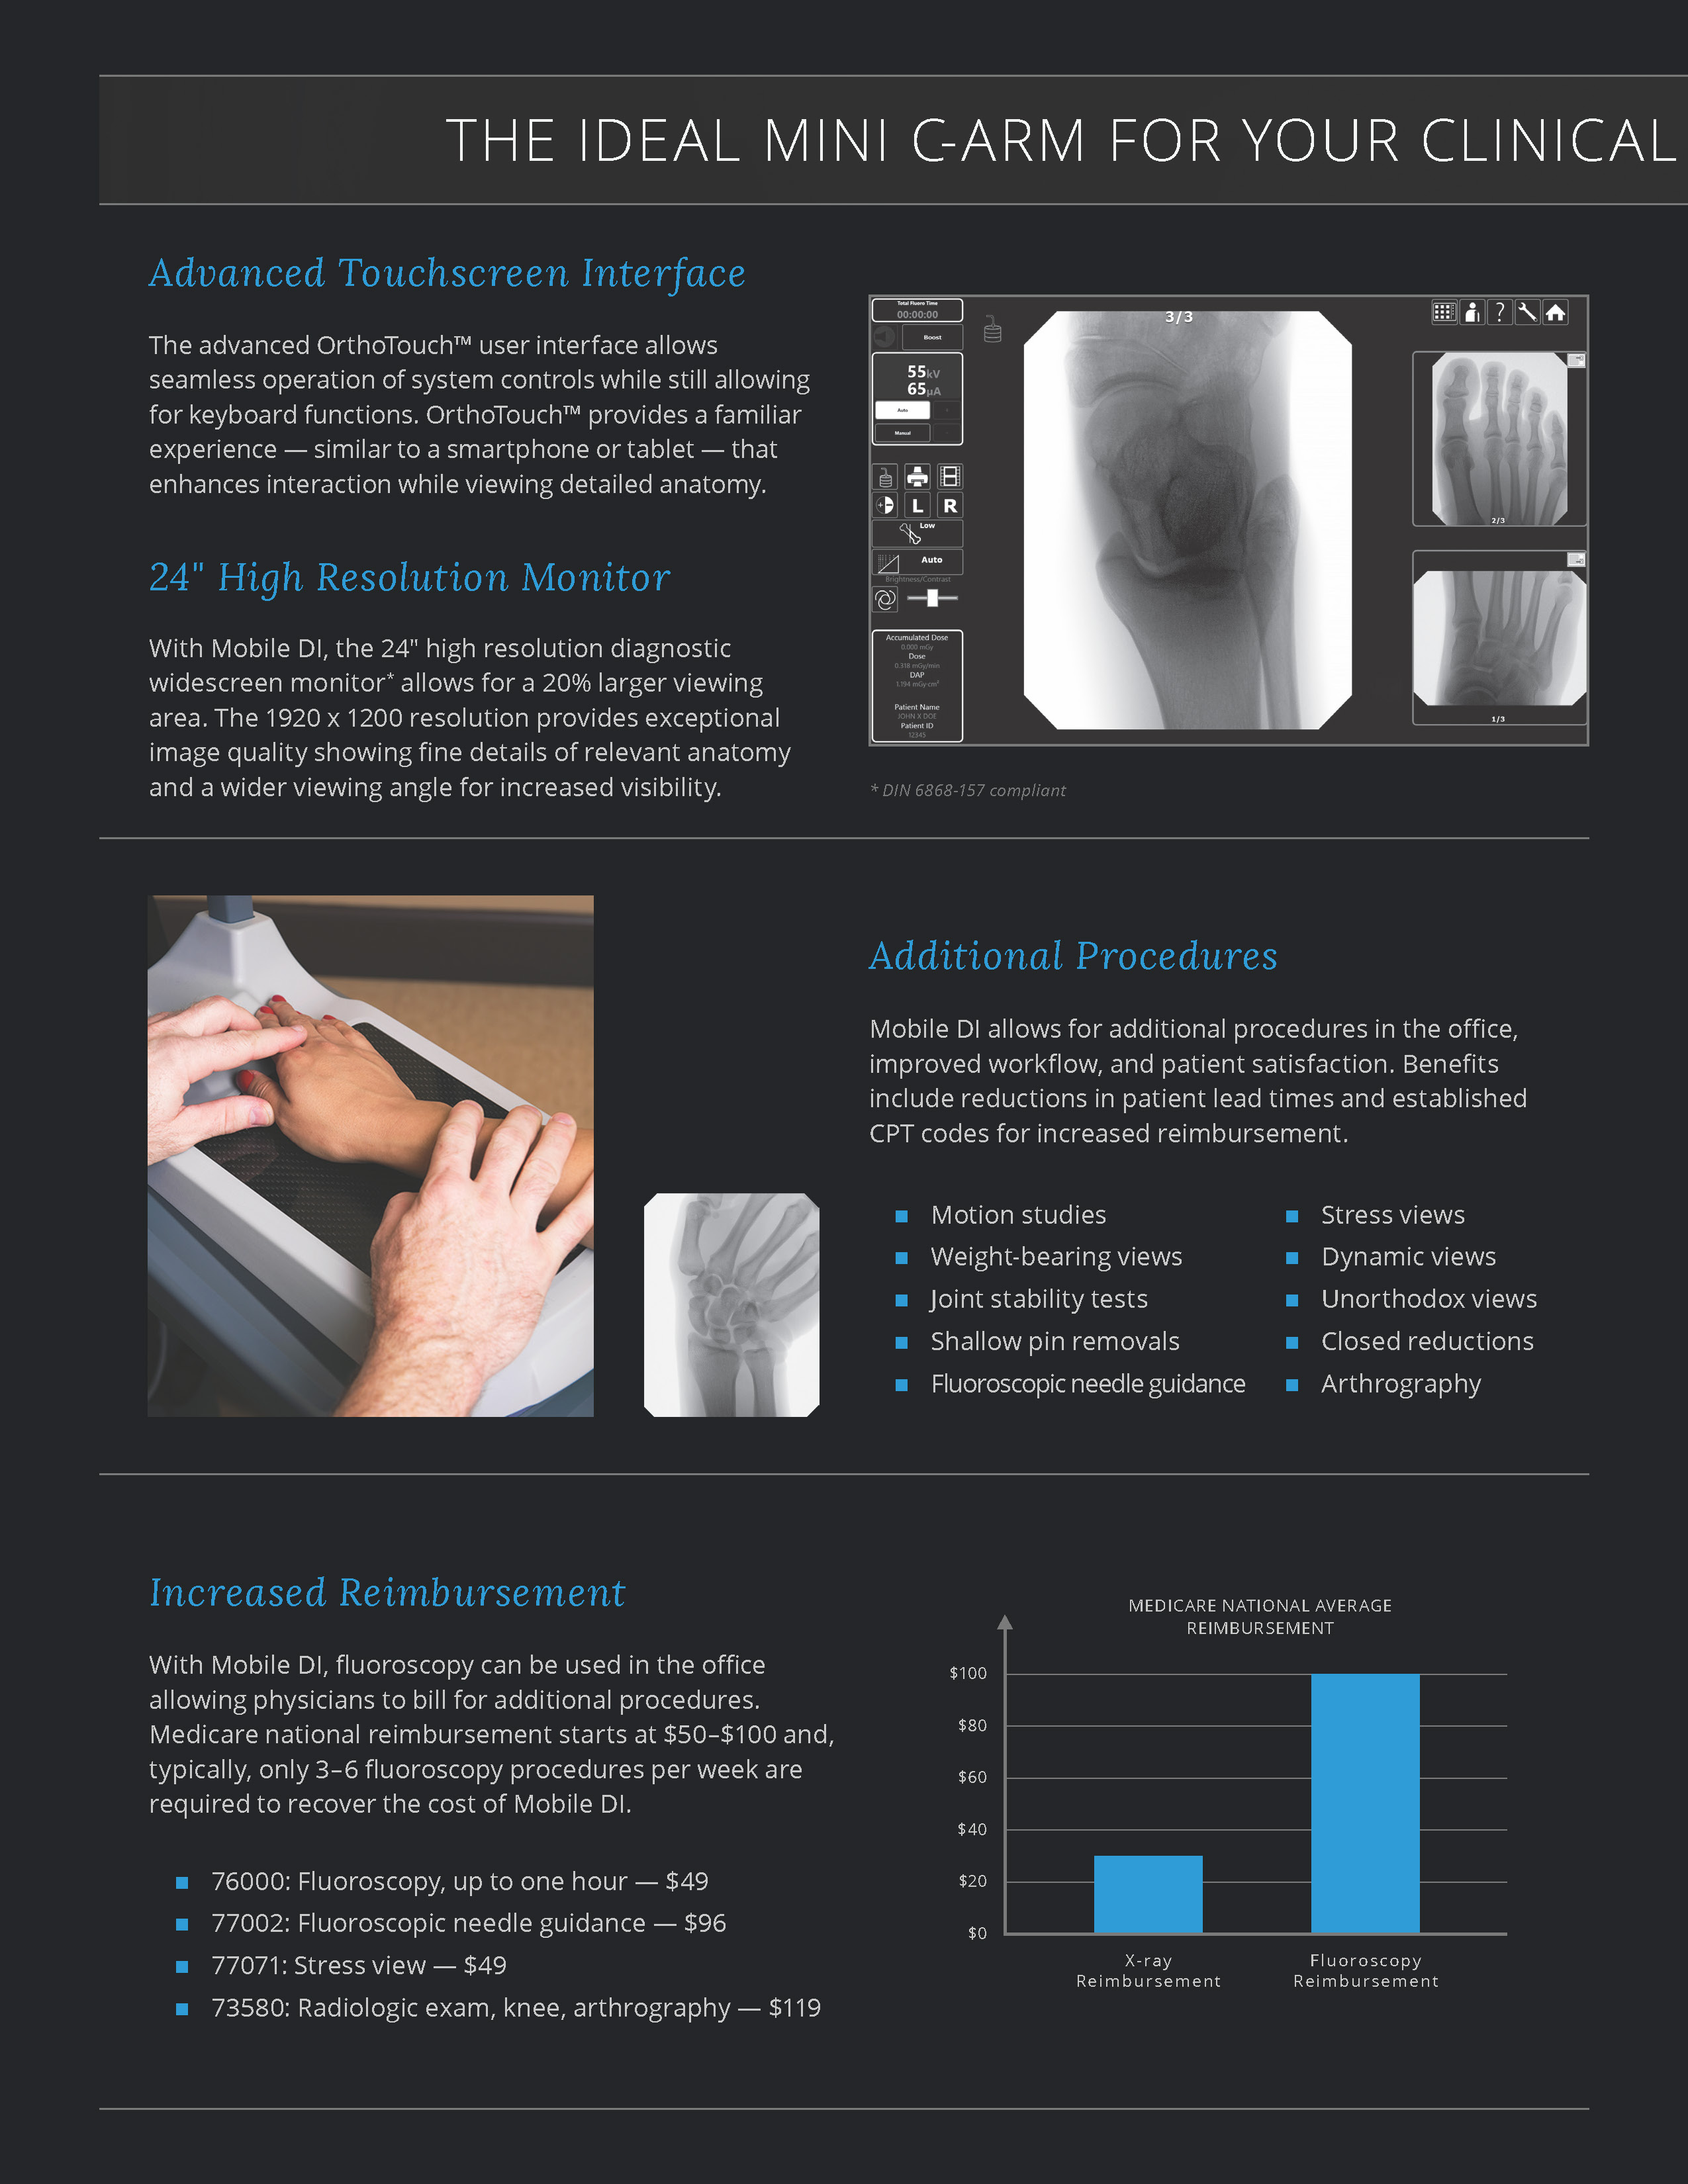

The Advanced Arthritis Relief Program (AARP) is a knee osteoarthritis (OA) treatment system that consists of fluoroscopic guided injections of Hyaluronic Acid, targeted Physical Therapy, and a special uploading Knee Brace. It’s MD, MP, and PA approved and covered by all major insurance carriers as well as Medicare.

2019 Fee Schedule & Coding Determination changes Osteoarthritis Joint Treatment & Pain Relief. After Standard of care for knee OA, MEDICARE requires patients try and fail viscosupplementation therapy prior to approving total knee arthroplasty (TKA). The AARP is this type of therapy that is approved by Medicare. It combines viscosupplementation with physical therapy and a specialized knee bracing procedure that has been delivering near perfect results.

2019 Fee Schedule & Coding Determination changes Osteoarthritis Joint Treatment & Pain Relief. After Standard of care for knee OA, MEDICARE requires patients try and fail viscosupplementation therapy prior to approving total knee arthroplasty (TKA). The AARP is this type of therapy that is approved by Medicare. It combines viscosupplementation with physical therapy and a specialized knee bracing procedure that has been delivering near perfect results.